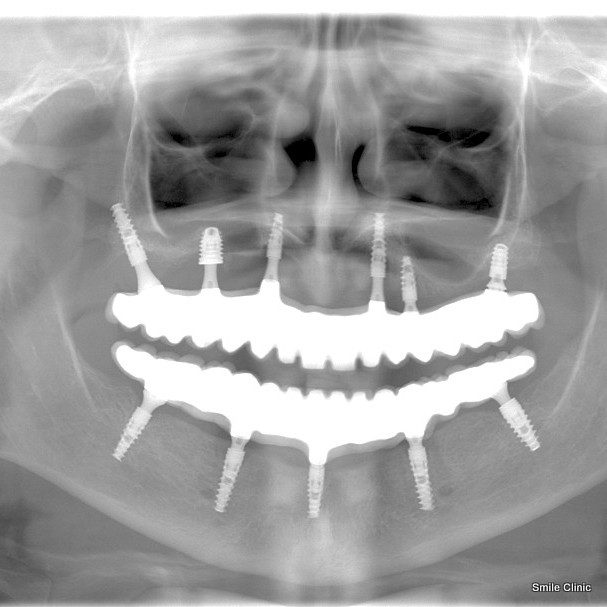

As you can see from the before and after photographs here, the result was amazing, and she’s now grinning like a Cheshire cat granted 9 lives.

6 dental implants to the upper jaw and 5 to the lower jaw, supporting 14 new teeth crowns per jaw formed in a bridge.